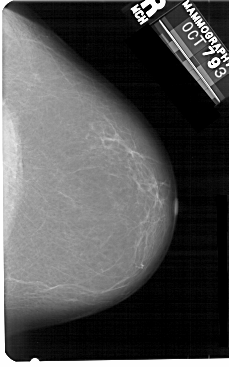

A_1476_1.RIGHT_MLO

RIGHT_MLO LINES 5491 PIXELS_PER_LINE 3526 BITS_PER_PIXEL 12 RESOLUTION 43.5 NON_OVERLAY